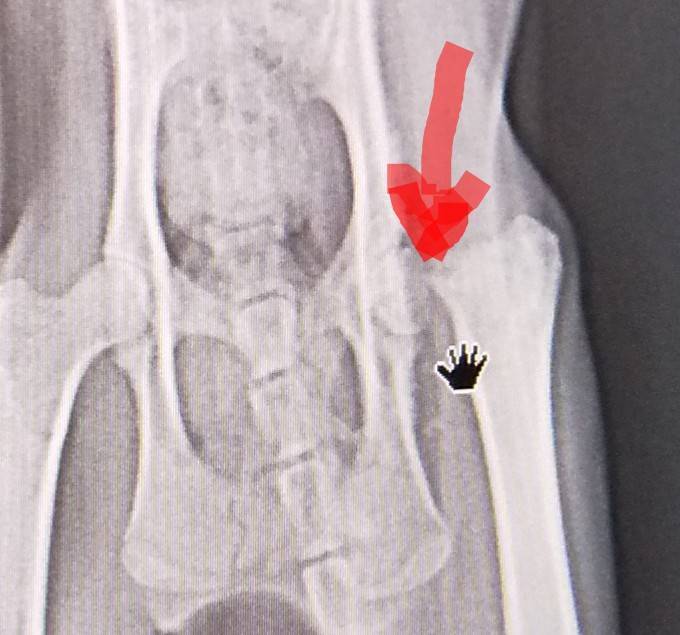

レントゲン③

骨折だけでなく骨の変形も見つかりました。

これは事故によるものというより先天性の奇形かもしれないとの事でした。